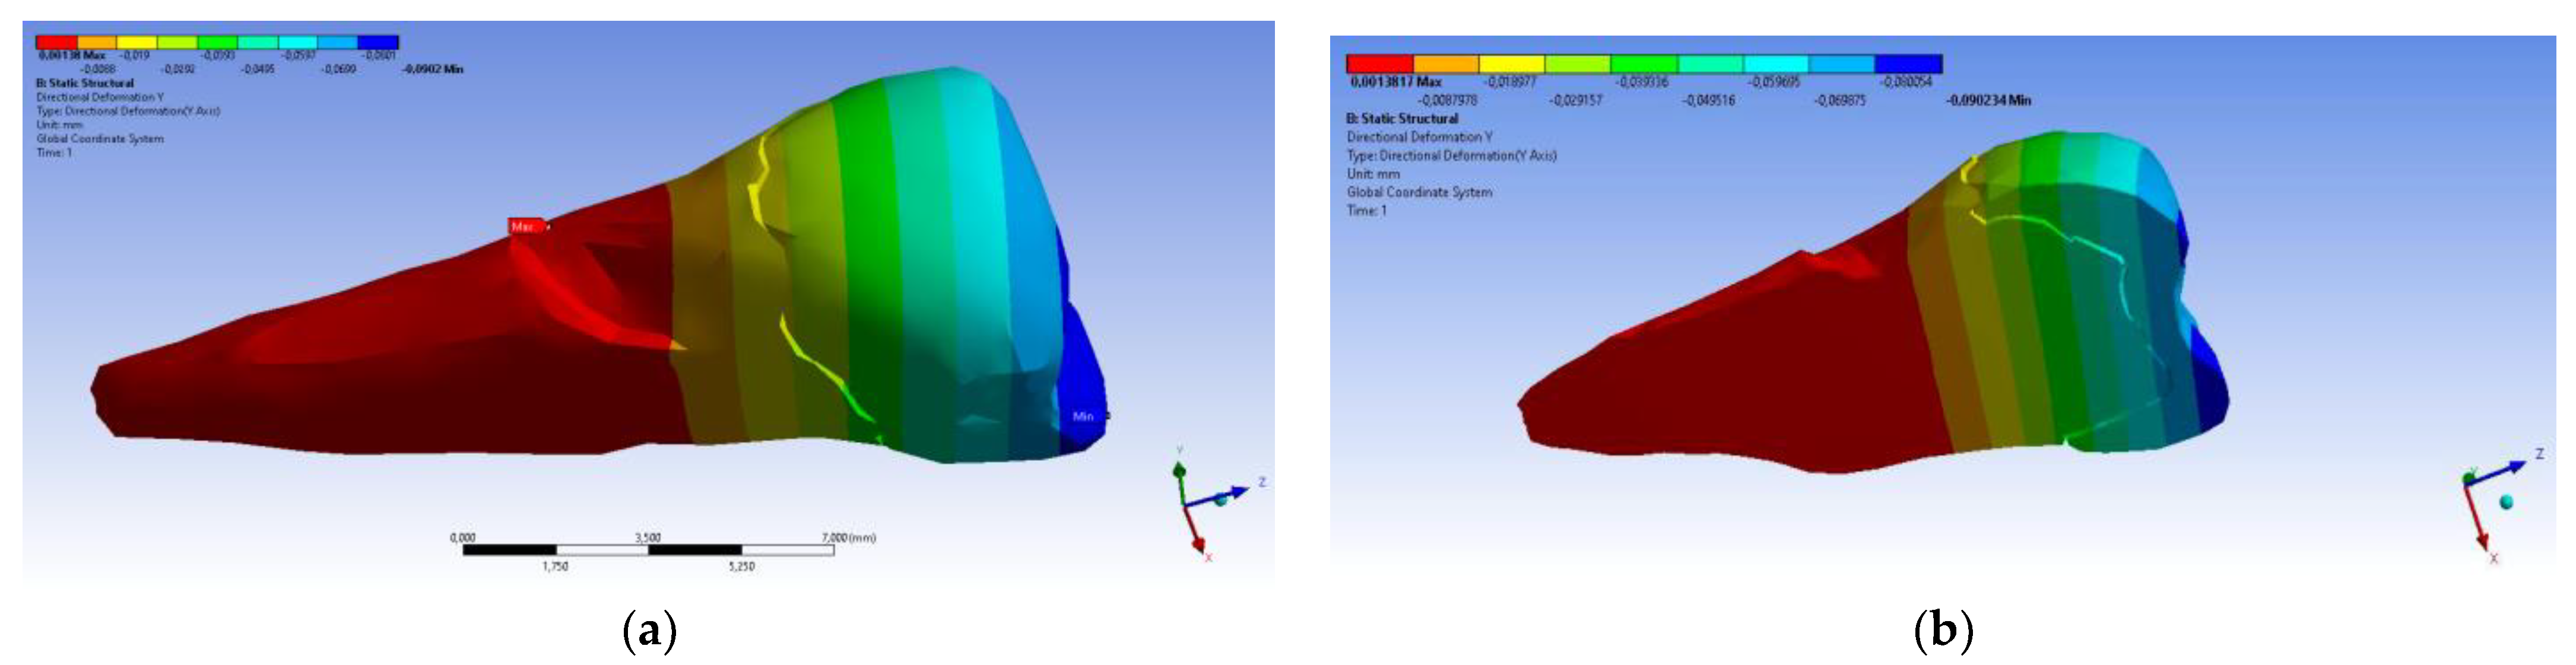

3. Finite Element Analysis (FEA) of Mandibular Right Premolars

| Minimum | 0 mm | −4.24 × 10−3 mm | −2.52 × 10−2 mm | −1.56 × 10−2 mm | 1.01 × 10−6 MPa | −35.6 MPa | −57.1 MPa | −104 MPa | −15.2 MPa | −152 MPa | −43.7 MPa | −39.6 MPa | −56.3 MPa |

| Maximum | 2.77 × 10−2 mm | 3.57 × 10−3 mm | 6.98 × 10−4 mm | 4.78 × 10−3 mm | 248 MPa | 61.5 MPa | 177 MPa | 72.2 MPa | 195 MPa | 21.4 MPa | 44.2 MPa | 117 MPa | 22.2 MPa |

| Minim. in | Cementum | Cementum | Enamel | Enamel | Cementum | Cementum | Enamel | Enamel | Enamel | Cementum | Enamel | Enamel | Cementum |

| Maxim. in | Enamel | Enamel | Cementum | Enamel | Cementum | Enamel | Enamel | Enamel | Enamel | Enamel | Cementum | Cementum | Cementum |